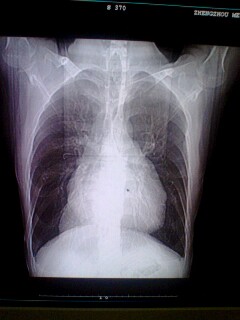

以下是引用clj20在2008-6-16 21:51:00的发言:[br]一、建议完善病史,加摄左、右侧位及胸部透视。[br] 二、就片论片。[br] (一)两肺血正常,心影呈普大型,双房双室增大。[br] 1、如果考虑风心,不考虑三尖瓣狭窄,而考虑二狭二闭。[br] 2、无病史,先心,心肌病等都有可能。[br] (二)右心膈角区阴影正位观[br] 1、纵隔占位:心包囊肿可能。[br] 2、下腔静脉,心包脂肪垫可能。[br]